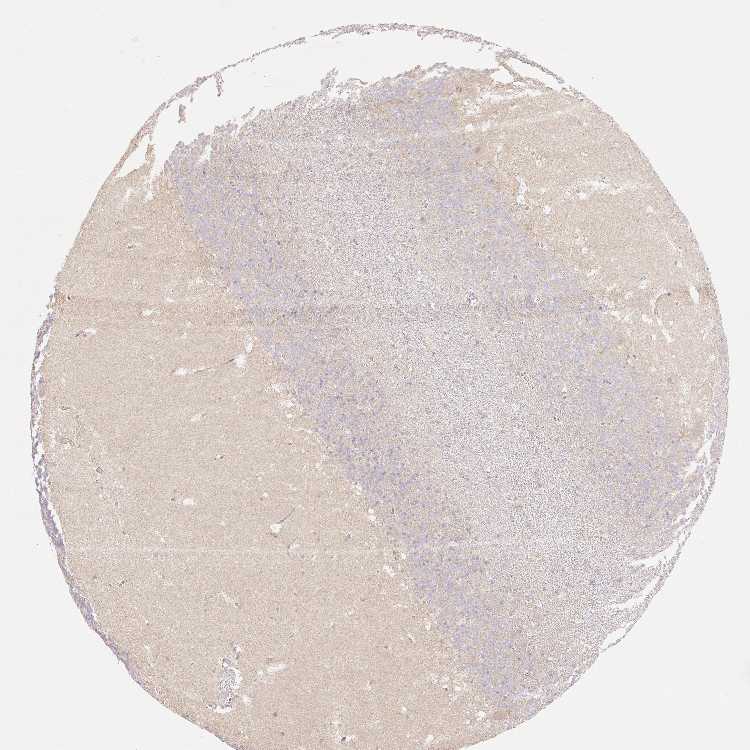

CEREBELLUM - Antibody stainingi

Antibody staining in the annotated cell types in the current human tissue is reported as not detected, low, medium, or high, based on conventional immunohistochemistry profiling in selected tissues. This score is based on the combination of the staining intensity and fraction of stained cells.

Each image is clickable and will lead to virtual microscopy that enables deeper exploration of all samples and also displays staining intensity scores, fraction scores and subcellular localization as well as patient and tissue information for each sample.

Antibody HPA052217Antibody HPA057284Antibody CAB004978

Purkinje cells Not detectedNot detectedMedium

Cells in granular layer LowNot detectedNot detected

Cells in molecular layer Not detectedNot detectedMedium